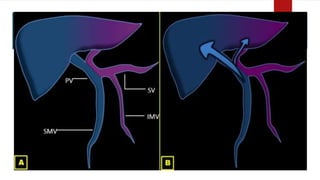

 Left lobe receives blood from

– Inferior mesenteric

– Splenic veins

 Right lobe receives blood from

– Superior mesenteric

– Portal veins

Streaming effect in portal circulation is causative.